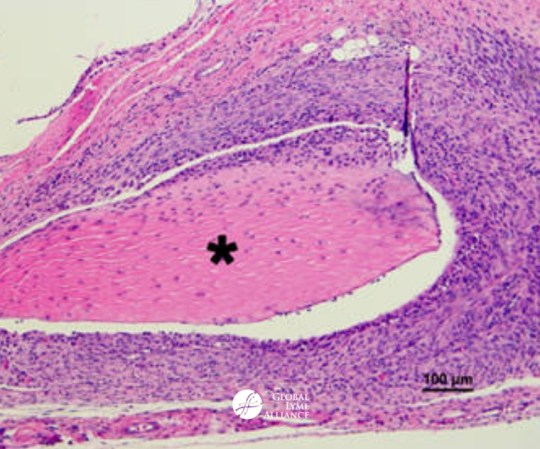

Pictured: Image of joint histopathology taken from a mouse infected with micro-colony/biofilm-like B. burgdorferi. Read Dr. Zhang’s full paper here.

Zhang et al. report that biofilm-like microcolony (MC) and planktonic (free-swimming spirochete and round body; SP) variants found in stationary phase cultures were not only more tolerant of exposure to antibiotics but also caused more severe arthritis in mice than the log phase spirochetes (LOG). Importantly, the authors show that the murine infection caused by LOG could be eradicated by Ceftriaxone (CefT) whereas the persistent infection established with MC could not be eradicated by Doxycycline (Doxy), CefT, or Vancomycin (Van), or Doxy+CefT or Van+CefT, but could only be eradicated by the persister drug combination Daptomycin (Dapto)+Doxy+CefT.

Zhang and colleagues published several influential papers over the past five years revealing a potential answer to this mystery. His lab showed that in vitro stationary phase (non-growing) cultures of B. burgdorferi contain different morphological variants. These bacterial variants include planktonic (free-swimming) spirochetal forms, round body forms, and aggregated microcolony (biofilm-like) forms, which have varying levels of persistence (e.g., the capacity to tolerate antibiotic exposure) in comparison to the log phase culture, which mainly consists of rapidly growing spirochetal forms with no or few persisters. B. burgdorferi develops into these morphological variants under stress conditions but their relevance to severe and persistent Lyme disease was unclear until the publication of this new study.